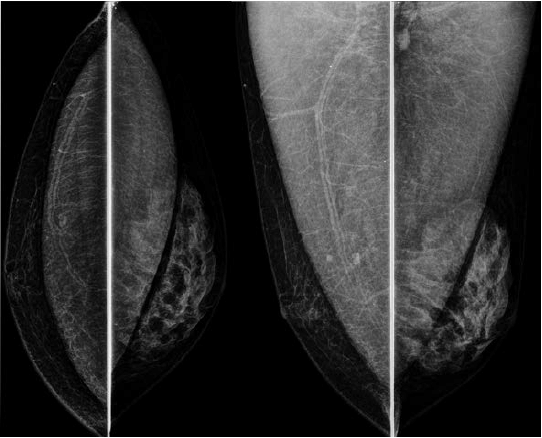

Assinale a alternativa que apresenta corretamente o que observa-se na análise das imagens da mamografia.

Uma paciente de 46 anos realizou esta mamografia.

Assinale a alternativa que contém a descrição e a classificação BIRADS correspondente.